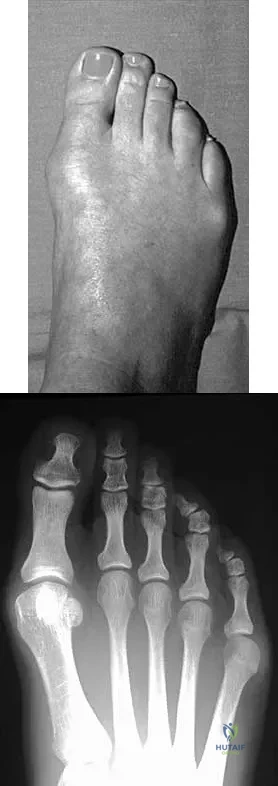

A 50-year-old woman has a painful hallux valgus and a painful callus beneath the second metatarsal head. A radiograph is shown in Figure 46. To correct these problems, treatment of the great toe deformity should consist of

Explanation